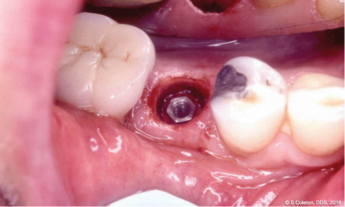

LightScalpel finds its roots in the revolutionary flexible CO2 laser fiber and all-metal CO2 laser tube technologies since it was introduced to dentists by Luxar Corporation () in 1991 as the first ever soft tissue surgical CO2 laser, designed specifically for a small office environment. Over 12,000 dentists, physicians, and surgeons worldwide enjoy the many praised clinical benefits and ease of use of the flexible fiber CO2 laser (see bloodless laser Stage II implant uncovering in Figure 1 and bloodless laser frenectomy in Figure 2).